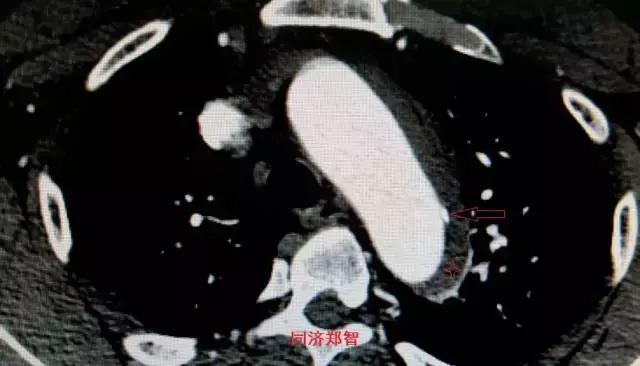

平扫CT提示主动脉弓层面及右肺动脉层面均可见主动脉血管腔内的内膜片影(红色箭头所示),CTA显示为A型主动脉夹层。